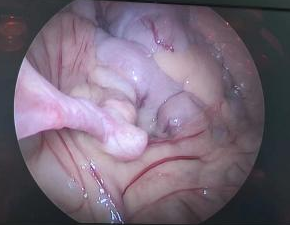

次日,小杰接受了腹腔镜(微创)手术,术中所见为经典的梅克尔憩室(头部由一根索带与脐部相连、基底部附着于系膜缘对侧与末端回肠相通),同时因为近期刚刚发生过出血,憩室浆膜轻度充血。最终孩子接受了憩室切除手术并重建了回肠的连续性,手术疤痕完全隐藏于脐部,体表未见任何刀疤。术后采用快速康复的治疗理念,早期喂养,促进胃肠功能恢复,1周后小杰顺利出院。

腔镜下见憩室头部由一索带连接至脐部

夹起憩室头部,离断滋养血管

肠切除肠吻合